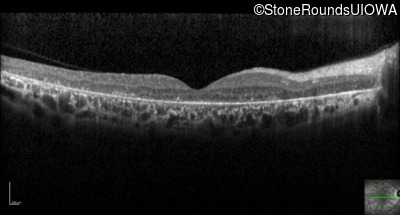

Optical Coherence Tomography - Right - 20/40 -1

Exemplar / OCT Stack

OCT Stack